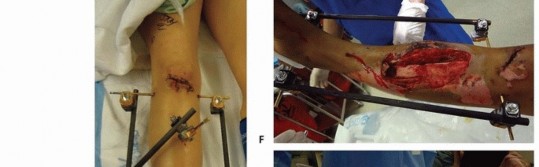

Knee-Spanning Fixator of Tibial Plateau Fracture Two Schanz pins are placed along the anterolateral thigh. These pins are placed in the midshaft region of the femur ( TECH FIG 5). Two Schanz pins are then inserted into the midshaft and distal tibia. Apply the tibial pins far enough away from the distal extension of the proximal tibia such that any future incisions required to perform definitive open reduction and internal fixation of the plateau fracture would not impinge on the pins.

### TECH FIG 5 • A. Open tibial plateau to be stabilized with knee-spanning fixator. B. Following a gentle manual reduction, the proposed location for eventual fixation incisions, as well as proposed pin sites, are marked on the skin. C. Two pins each above (distal femur) and below (mid tibia) the plateau fracture zone of injury are applied.

(continued)

A solitary bar can then be used to span all pins. Longitudinal traction is applied and reduction confirmed under fluoroscopy. Slight flexion of the knee is maintained and all connections are tightened to maintain the ligamentotaxis reduction. Alternatively, the proximal two femur pins can be connected using a single bar and the two tibial pins with a second bar. These two bars can then be manipulated to achieve a reduction of the plateau, and a third bar connecting the proximal femoral and distal tibial bars is then attached and tightened to maintain the reduction. A large monotube fixator can also be used in this fashion to span the knee and maintain a temporary reduction. 542

### TECH FIG 5 •

D,E. One single bar connects the proximal two pins to the distal two pins. The fracture is then reduced and the clamps tightened. A second bar was added for stability, bridging the fracture.